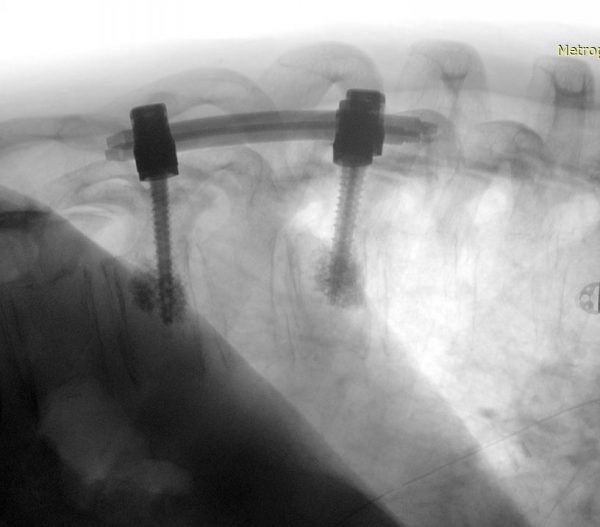

Χειρουργική Αντιμετώπιση: Οι ενδείξεις και ο τρόπος χειρουργικής αντιμετώπισης εξαρτώνται απολύτως από τον τύπο του όγκου. Πρωτοπαθείς (μη-μεταστατικοί) όγκοι των σπονδύλων χρειάζονται ριζική αφαίρεση με σπονδυλεκτομές. Σε περίπτωση μεταστάσεων συνήθως αρκεί η αποσυμπίεση των νευρικών δομών και η συμπληρωματική ακτινοβολία. Το αν υπάρχει ένδειξη για χειρουργείο σε ασθενή με μεταστατική νόσο σπονδυλικής στήλης είναι κάτι που πρέπει να συζητηθεί και να συναποφασιστεί με τους ογκολόγους. Για ενδοσκληρίδους όγκους όπως πχ. μηνιγγιώματα ή νευρινώματα, καθώς επίσης για ενδομυελικούς όγκους (πχ. αστροκυττώματα ή επενδυμώματα) η θεραπεία είναι η ολική χειρουργική αφαίρεση. Συνήθως χρησιμοποιούνται ελάχιστα επεμβατικές μέθοδοι ενώ αποφεύγεται η καταστροφή των υγιών ιστών και δομών της σπονδυλικής στήλης (Εικόνα 3). Μερικοί όγκοι, όπως πχ. το λίπωμα νωτιαίου μυελού, αφαιρούνται ιδιαίτερα αποτελεσματικά με τη χρήση λέιζερ (laser) (Εικόνα 4).

Εικόνα 3: Αριστερά: Αποκάλυψη της μήνιγγας, λίγο πρίν τη διάνοιξή της για ενδομυελικό όγκο. Δεξιά: Μετά την ολοκλήρωση της αφαίρεσης της βλάβης, επανατοποθέτηση των ακανθωδών αποφύσεων και αποκατάσταση της ανατομίας της σπονδυλικής στήλης (Πεταλοπλαστική).(προσωπικό αρχείο νευροχειρουργού Π. Σταυρινού).